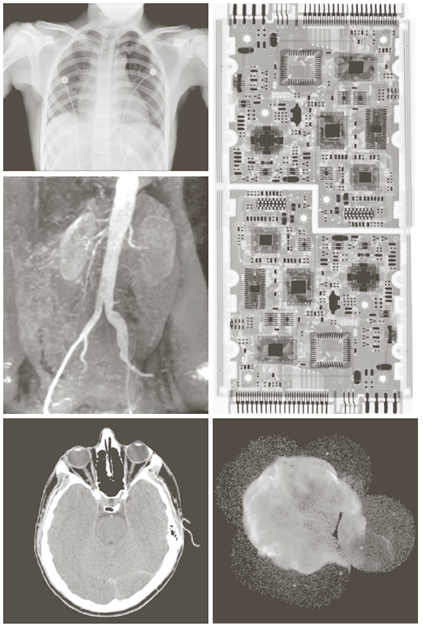

X-ray image

• X선의 투과성을 이용

Image